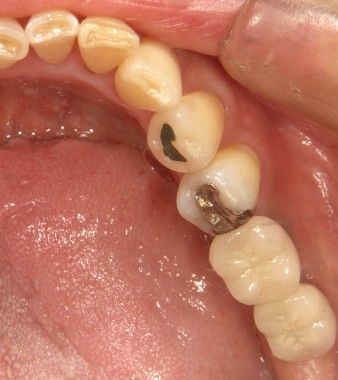

インプラントの術前・術後 Kさん